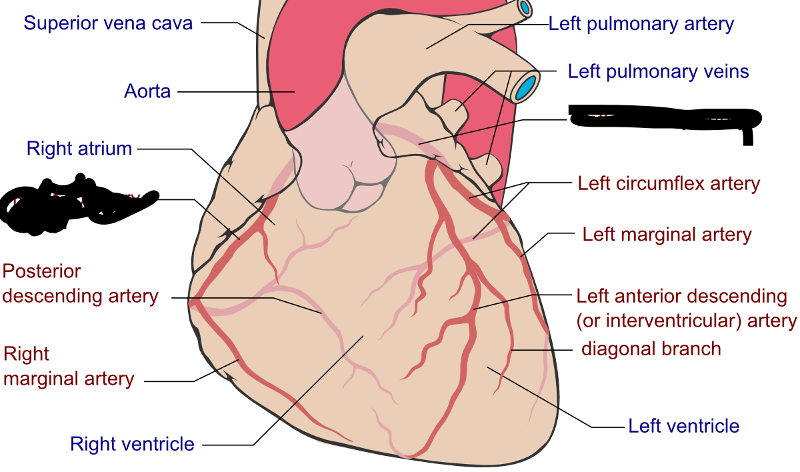

Anterior interventricular sulcus

Circumflex branch (of the left coronary artery)

interventricular branch of the left coronary artery. = left anterior descending artery (LADA))

Left/right coronary artery

Left/right atrium

left/right ventricle

Superior/inferior vena cava